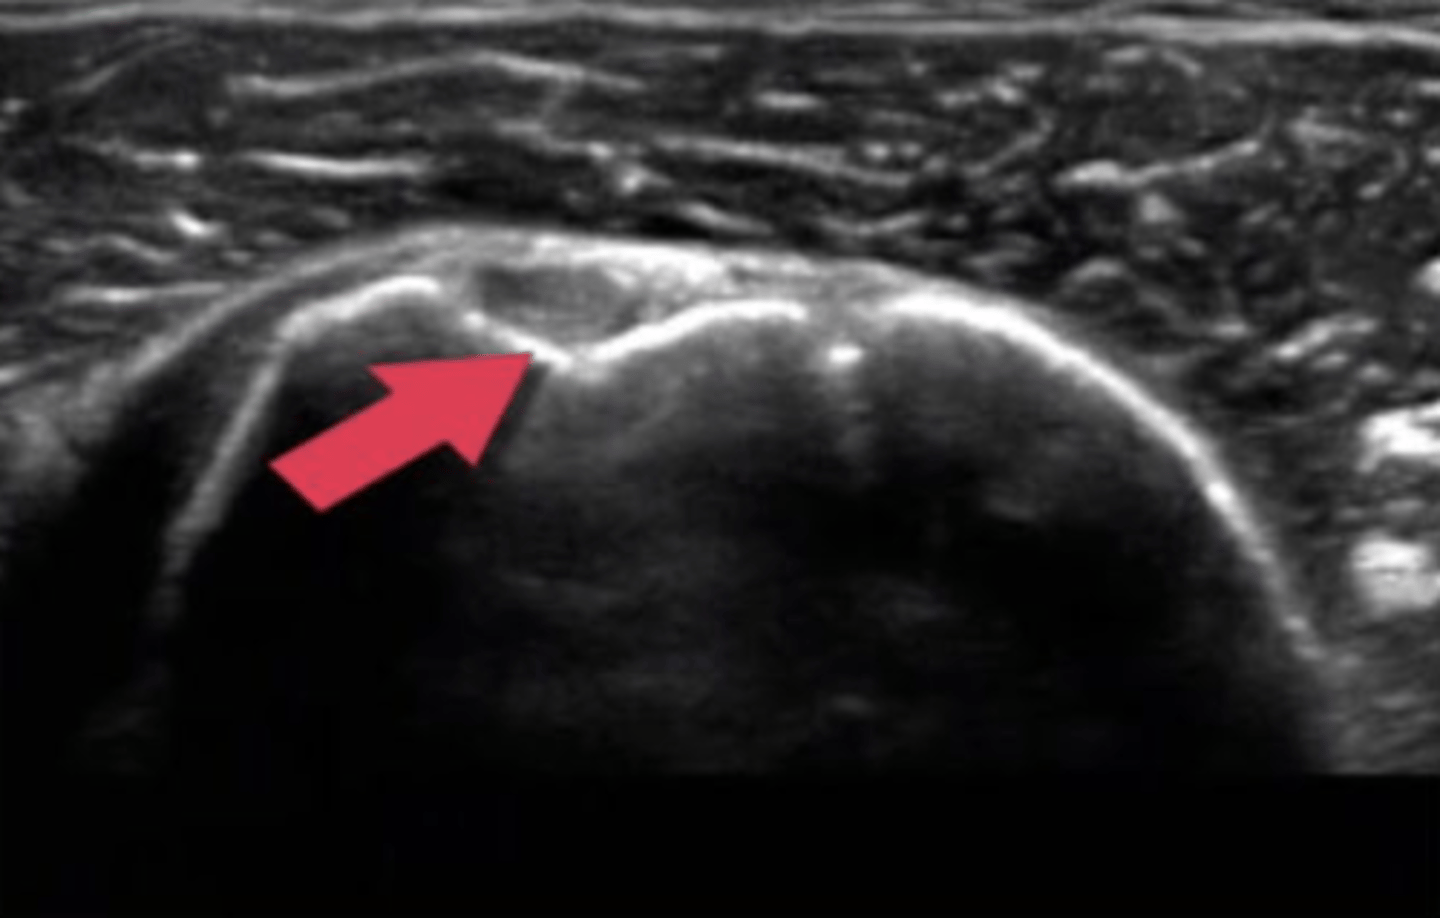

ultrasound, transverse

What type of imaging is this and how is it being viewed?

a. ultrasound, longitudinal

b. T2 MRI, frontal

c. CT Scan, axial

d. ultrasound, transverse